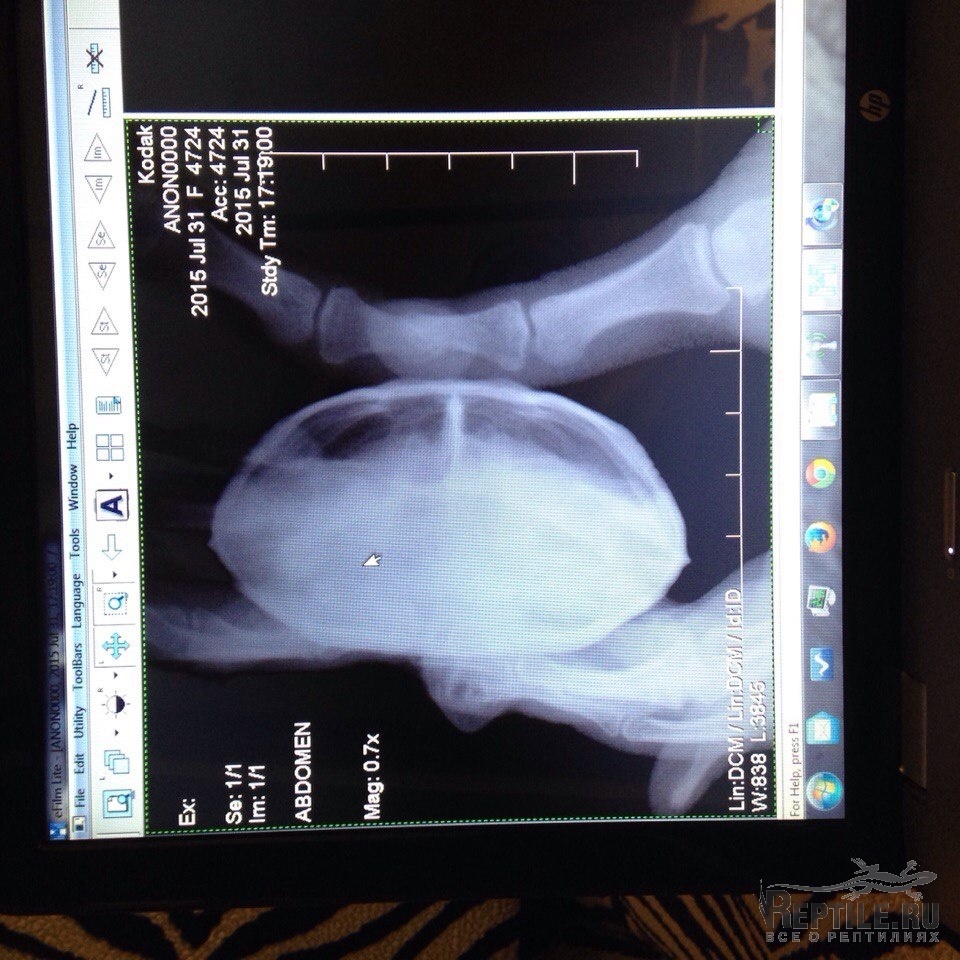

Был сделан цифровой рентген и по этим снимкам можно что то сказать?

У меня складывается ощущение, что пол легкого правда в мутке